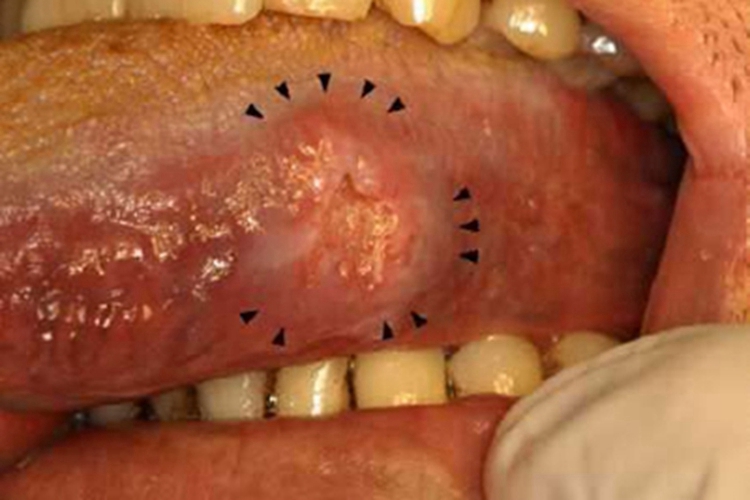

舌癌表现为舌糜烂、溃疡或肿块,伴有舌痛,疼痛可反射至耳部。

舌癌表现为舌糜烂、溃疡或肿块,伴有舌痛,疼痛可反射至耳部,可伴有流涎、口臭、舌运动障碍,咀嚼、语言、吞咽等功能障碍等,建议尽早治疗,以免出现转移症状。